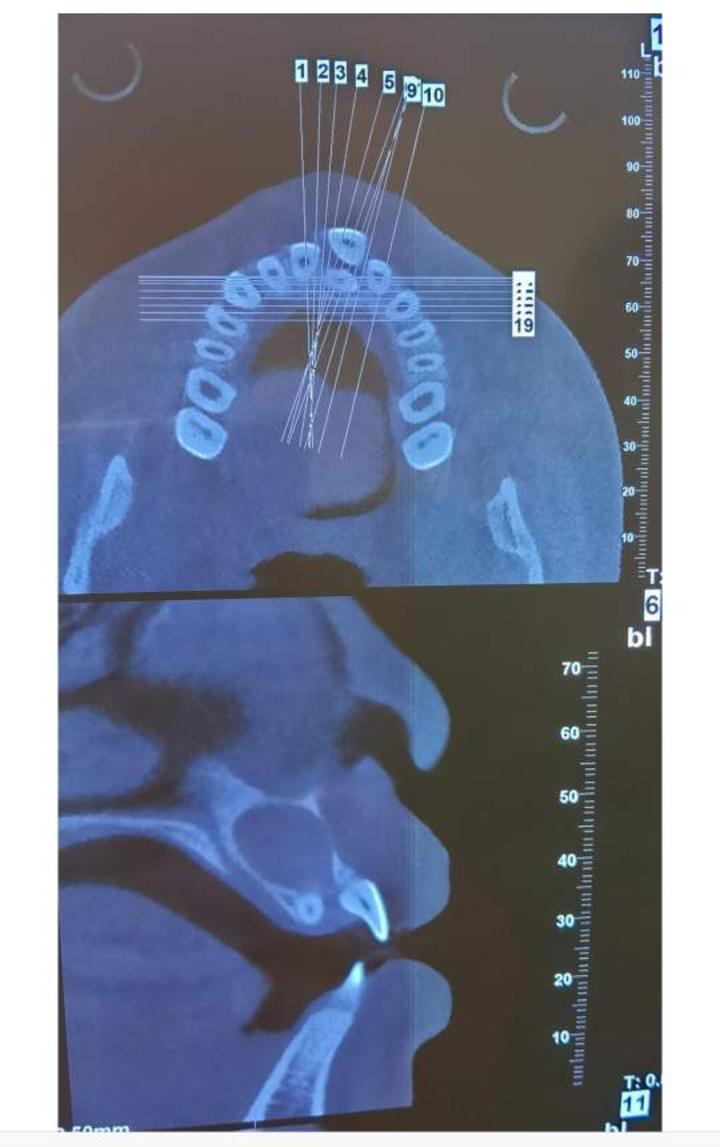

3.恒牙、乳牙阻生,不能萌出